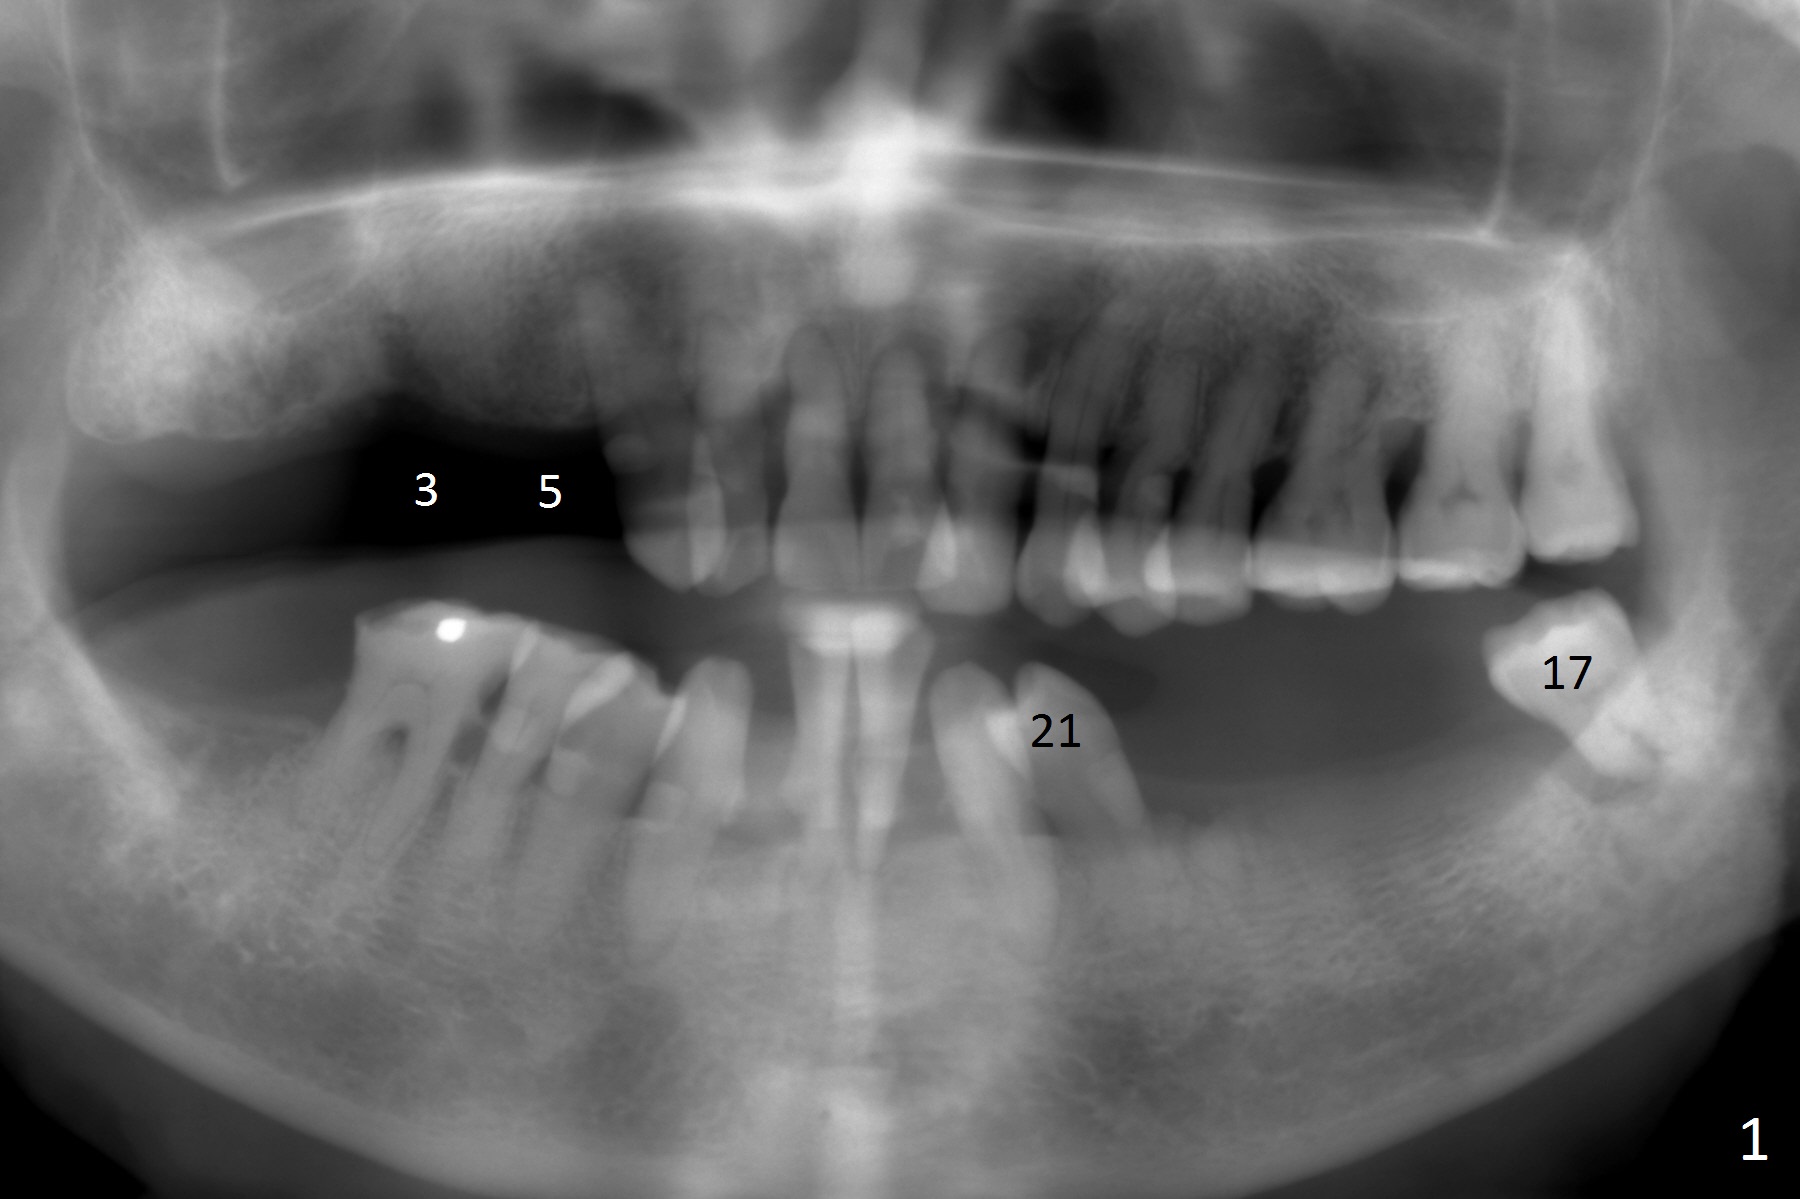

A 83-year-old woman requests lower RPD to replace #18-20 and 23-26 (Fig.1), although UR FPD supported by implants at #3 and 5 (Fig.2,3) is a better option. For the RPD, an implant will be placed at #18 (Fig.4) or 17 (Fig.5) with ball abutment. At #18, a shorter implant will be placed at the top of the Inferior Alveolar Canal (brown), while at #17, a longer implant will be placed buccal (B) to the canal.